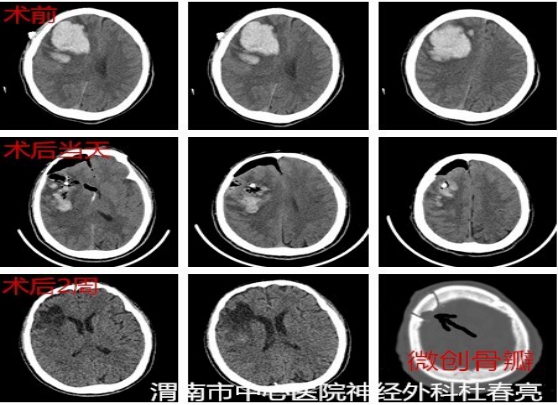

患者王某,男,61岁,入院前突发左侧肢体活动不灵伴意识障碍2小时。查体时显示神志不清,昏迷状态,头颅CT结果显示:右侧基底节区脑出血约40ml。

入院后,在白西民主任、姚胜副主任组织下,党俊涛主任医师及冯毅副主任医师协作,由杜春亮主治医师、王小峰医师及王举医师实施手术。避开重要的血管和神经,取右额平行于中线纵形切口长约4cm,骨窗直径2.5cm,经额叶顺穿刺将套筒准确置入患者大脑深部的血肿腔,建立供内镜通过的微小孔道,再置入圆珠笔芯粗细内镜,以提供良好的照明和视野,很快就准确彻底地清除了深藏脑内的淤血。术后CT显示血肿清除干净,目前患者神志清楚,已康复出院。

据了解,内镜套筒辅助清除术,是通过一个微小的孔道,在内镜直视下清除脑内淤血,避免了传统开颅手术的损伤和钻孔引流手术的盲目,能有效止血、迅速清除血肿,更加符合微创和安全的原则。这一微创技术在医院的进一步推广,将革新传统脑出血的手术理念,并使更多的脑出血患者受益。